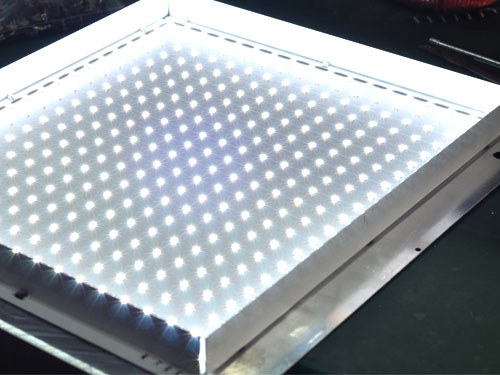

(左圖為錦德等距點直射式LED光源布局圖,右圖為導光板光源布局圖)

(圖為錦德觀片燈觀察屏亮度分布均勻,均勻性大于90%,無閃爍,無暗區)

(圖為等距點陣式LED燈珠)